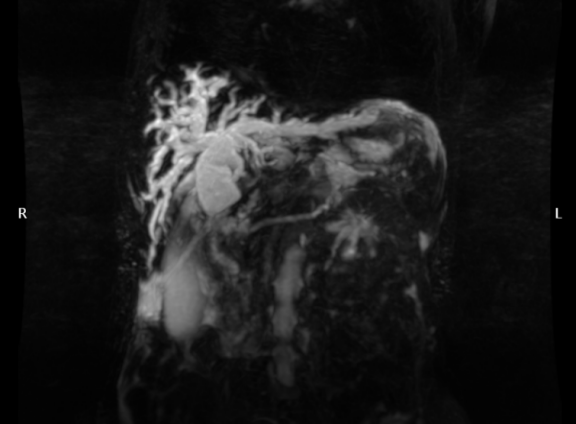

患者女性,因惡性腫瘤致膽道梗阻,術(shù)前MRCR、彩超報(bào)告:胰頭占位,肝內(nèi)外膽管擴(kuò)張,查體和檢驗(yàn)表現(xiàn)為全身黃疸和肝功能損害持續(xù)加重,若不及時(shí)進(jìn)行膽道引流減壓,可能因肝功能衰竭和感染中毒性休克危及生命。經(jīng)科室緊急討論和多學(xué)科專(zhuān)家會(huì)診,一致認(rèn)為應(yīng)及時(shí)行經(jīng)皮肝穿刺膽道引流術(shù)(PTCD),以達(dá)到“減黃”緩解膽道壓力,遏制肝功能持續(xù)惡化,防范感染中毒性休克,為緩解癥狀體征和后續(xù)診療提供保障。

術(shù)前CT和B超顯示肝內(nèi)外膽管擴(kuò)張